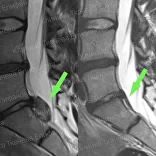

* Резорбция — процесс уменьшения грыжи диска за счет естественных физиологических способностей организма. Это основа эффективного лечения грыжи и альтернатива операции.

Метод модулируемой резорбции позволяет ускорить этот процесс, взять боль под контроль и улучшить качество жизни.